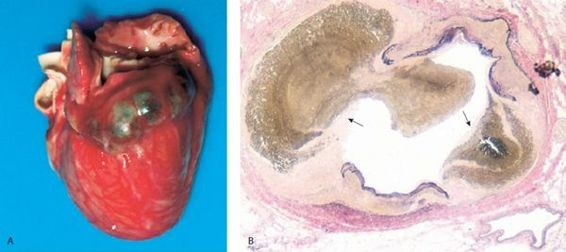

El compromiso cardíaco es la manifestación más importante de la enfermedad de Kawasaki.

Cerca del 15% al 25% de los niños desarrollan alteraciones coronarias, manifestadas por dilatación arterial coronaria y desarrollo de aneurisamas, confirmadas en la ecocardiografía 2D. Las manifestaciones del compromiso arterial coronario incluyen signos y síntomas de isquemia de miocardio y raras veces, infarto de miocardio manifiesto o ruptura de un aneurisma. También puede haber pericarditis, insuficiencia mitral, derrames pericárdicos, miocarditis, endocarditis, insuficiencia aórtica, insuficiencia cardíaca y arritmias. La tasa de mortalidad estimada por enfermedad de Kawasaki es del 2% y, por lo general, se debe al compromiso cardíaco, casi siempre durante la fase de convalecencia de la enfermedad, por trombosis o aneurismas arteriales coronarios.